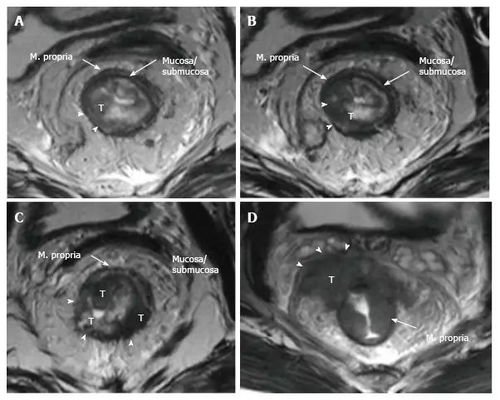

切口转移的临床表现主要包括局部肿块增大、质地变硬或疼痛等。如果出现这些症状伴随体重下降、持续发热等全身症状时,应高度警惕肿瘤扩散的可能性。为了早期发现转移灶,患者应该定期进行影像学检查(如CT、MRI)和淋巴结触诊。